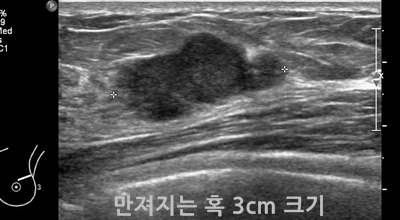

유방 밖으로 퍼진 악성 종양으로 생명을 위협할 수 있습니다. 유방암은 보통 유방의 유관과 소엽에서 발생하는데요 남성도 드물게 유방암에 걸릴 수 있습니다. 유방암은 아직 명확한 원인이 노출되지 않았습니다. 하지만 다양한 위험 요인을 추정할 수 있는데요 유전, 호르몬, 노화, 음주, 비만 등이 있어요. 가장 흔한 증상은 유방에 생기는 종괴입니다. 그리고 유두 분비, 유방통, 피부궤양, 함몰, 겨드랑이 종괴 등이 나타날 수 있습니다. 증상들이 반드시 유방암을 나타내는 것은 아닐 수도 있기 때문에 정확한 검사가 필요하다고 합니다.